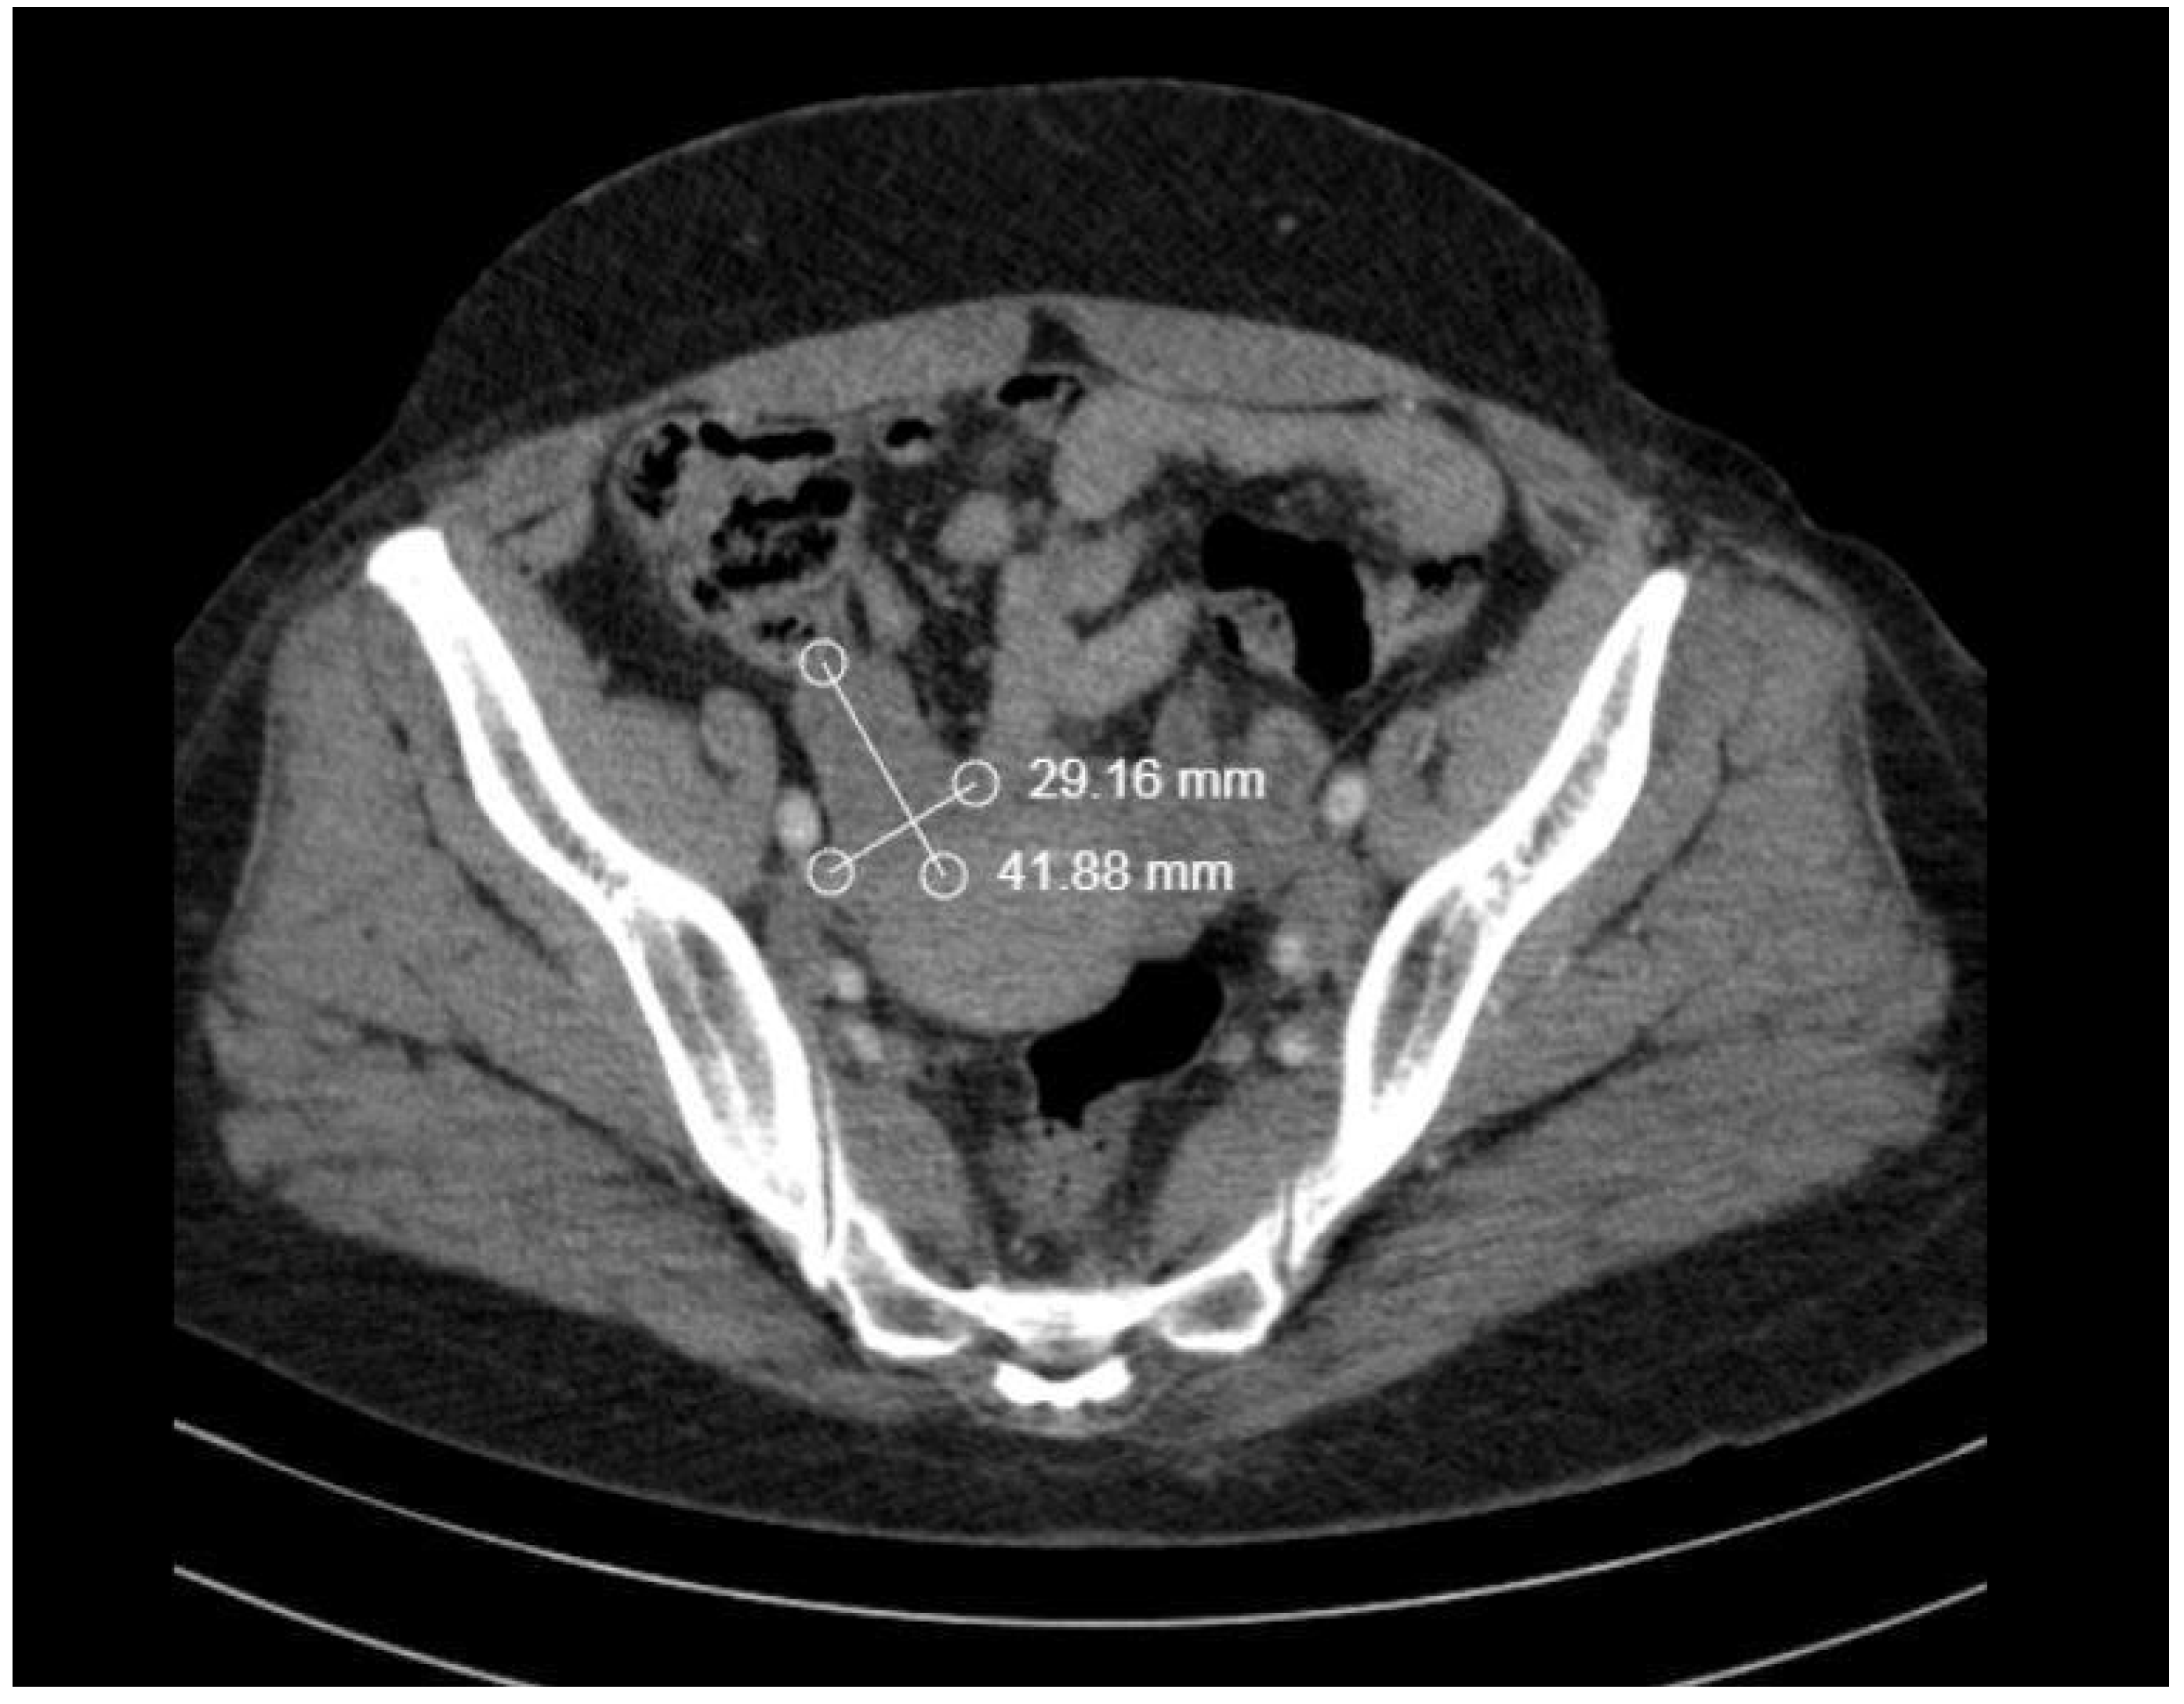

2. Case Report